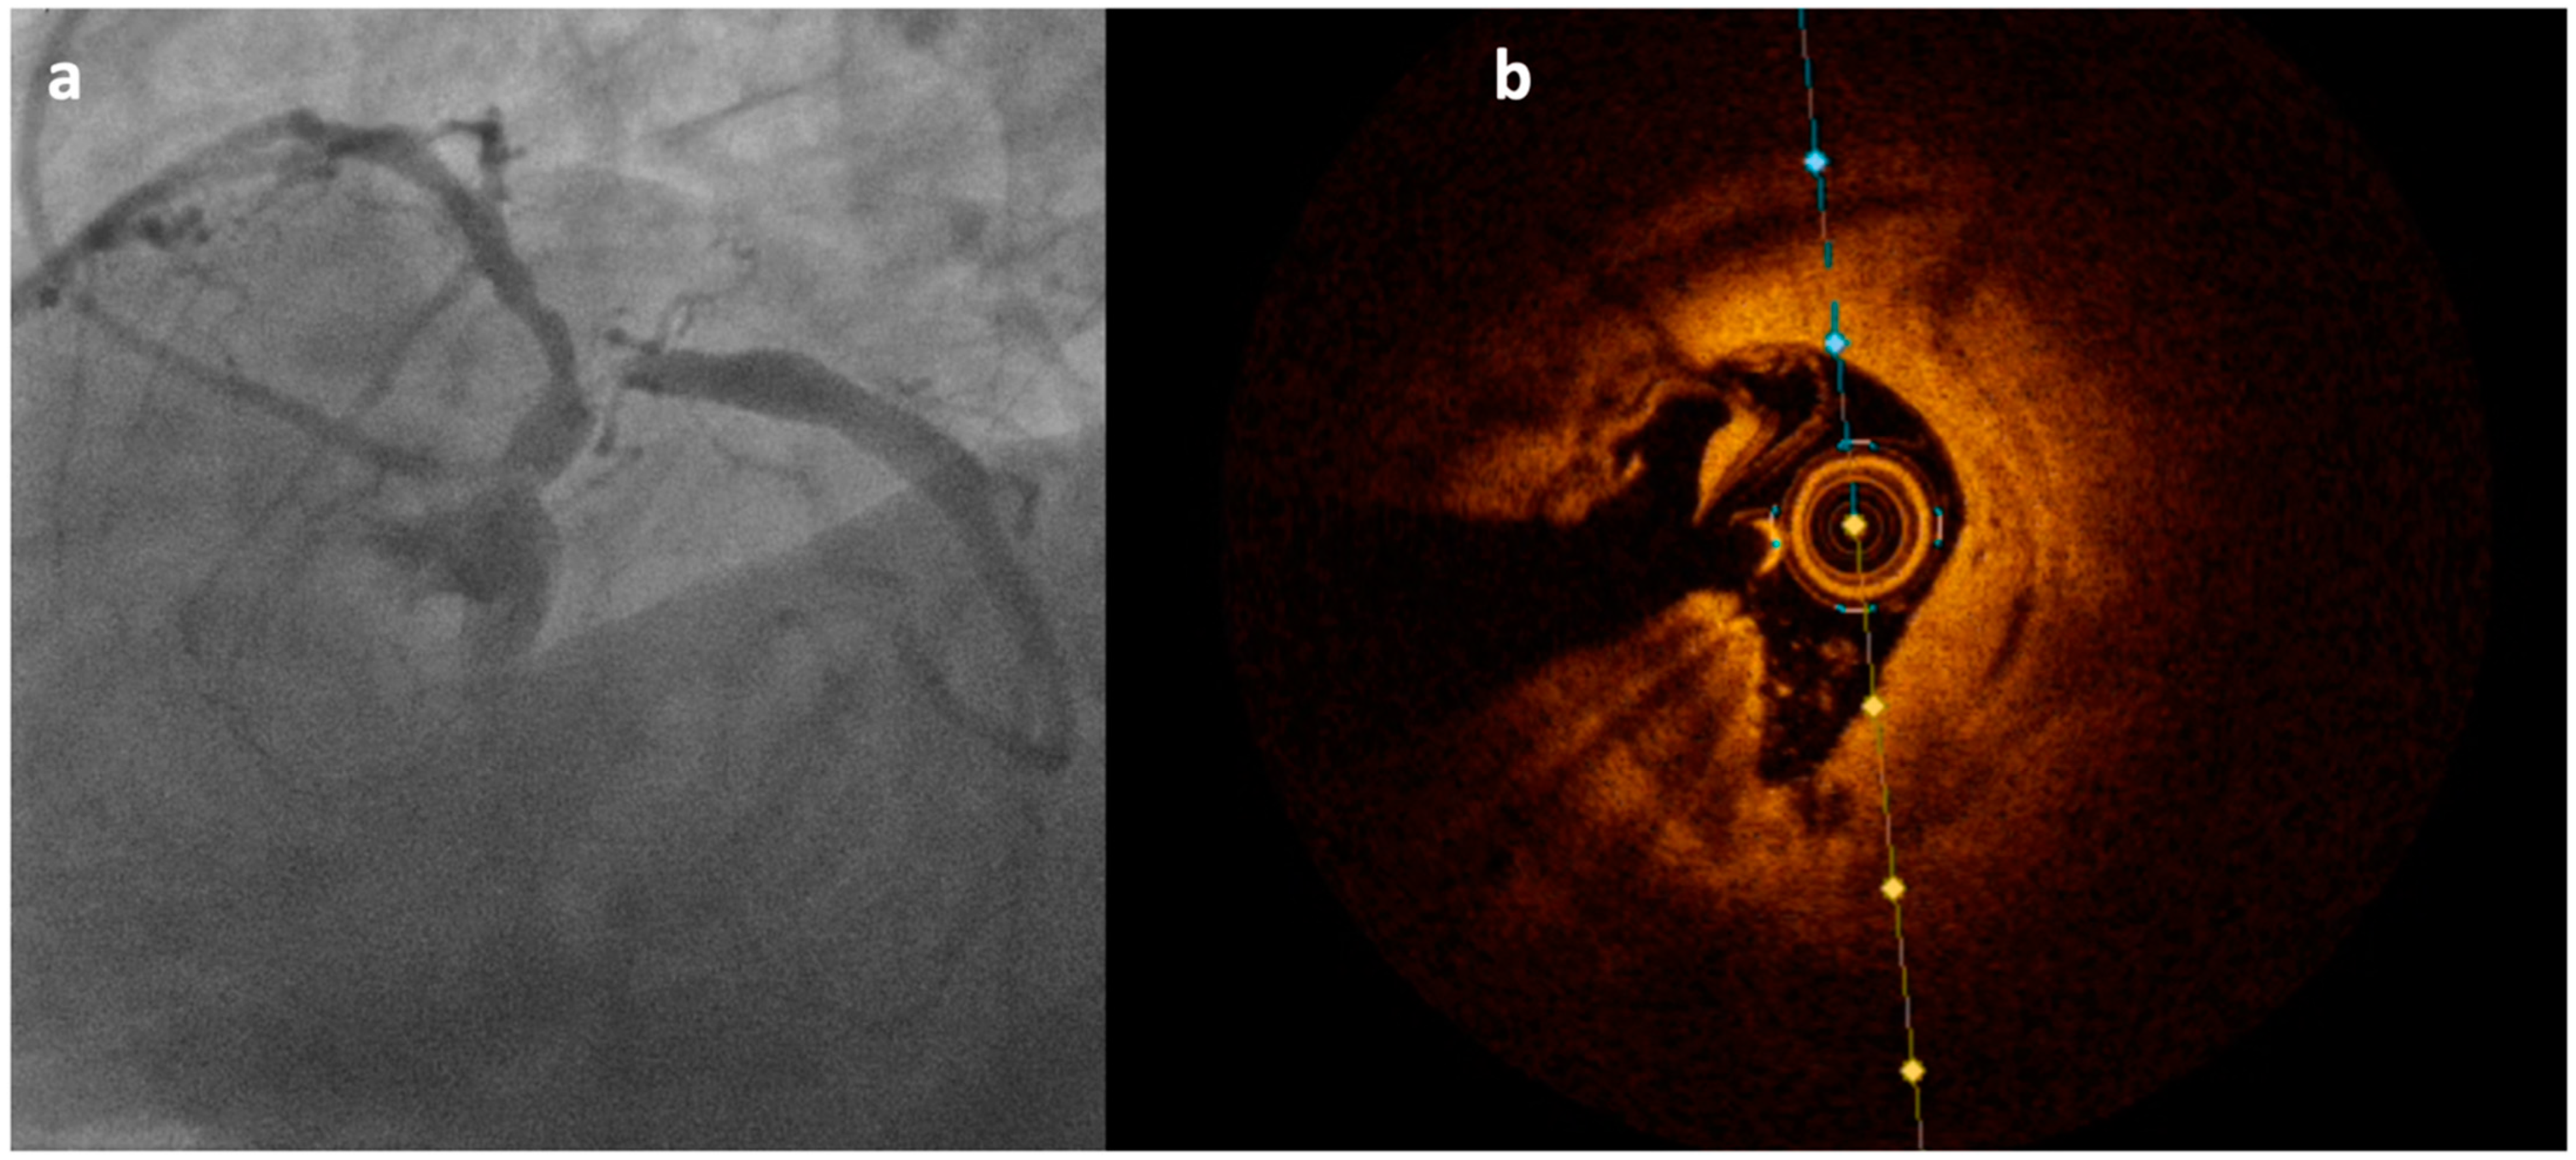

3.4. Optical Coherence Tomography (OCT)

4. Imaging-Guided Plaque Modification

- Ali, Z.A.; Galougahi, K.K.; Mintz, G.S.; Maehara, A.; Shlofmitz, R.A.; Mattesini, A. Intracoronary optical coherence tomography: State of the art and future directions. Eurointervention 2021, 17, e105–e123. [Google Scholar] [CrossRef] [PubMed]

- Ali, Z.A.; Galougahi, K.K. Shining light on calcified lesions, plaque stabilisation and physiologic significance: New insights from intracoronary OCT. Eurointervention 2018, 13, 2105–2108. [Google Scholar] [CrossRef]